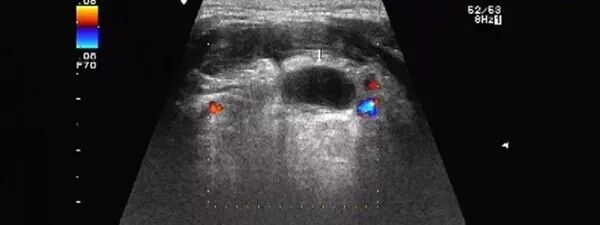

侧方声影和回声失落

声束通过囊肿边缘或肾上下极侧边时,可以由于折射而产生边缘声影或侧边“回声失落”。

改变扫查角度有助于识别这种伪像。